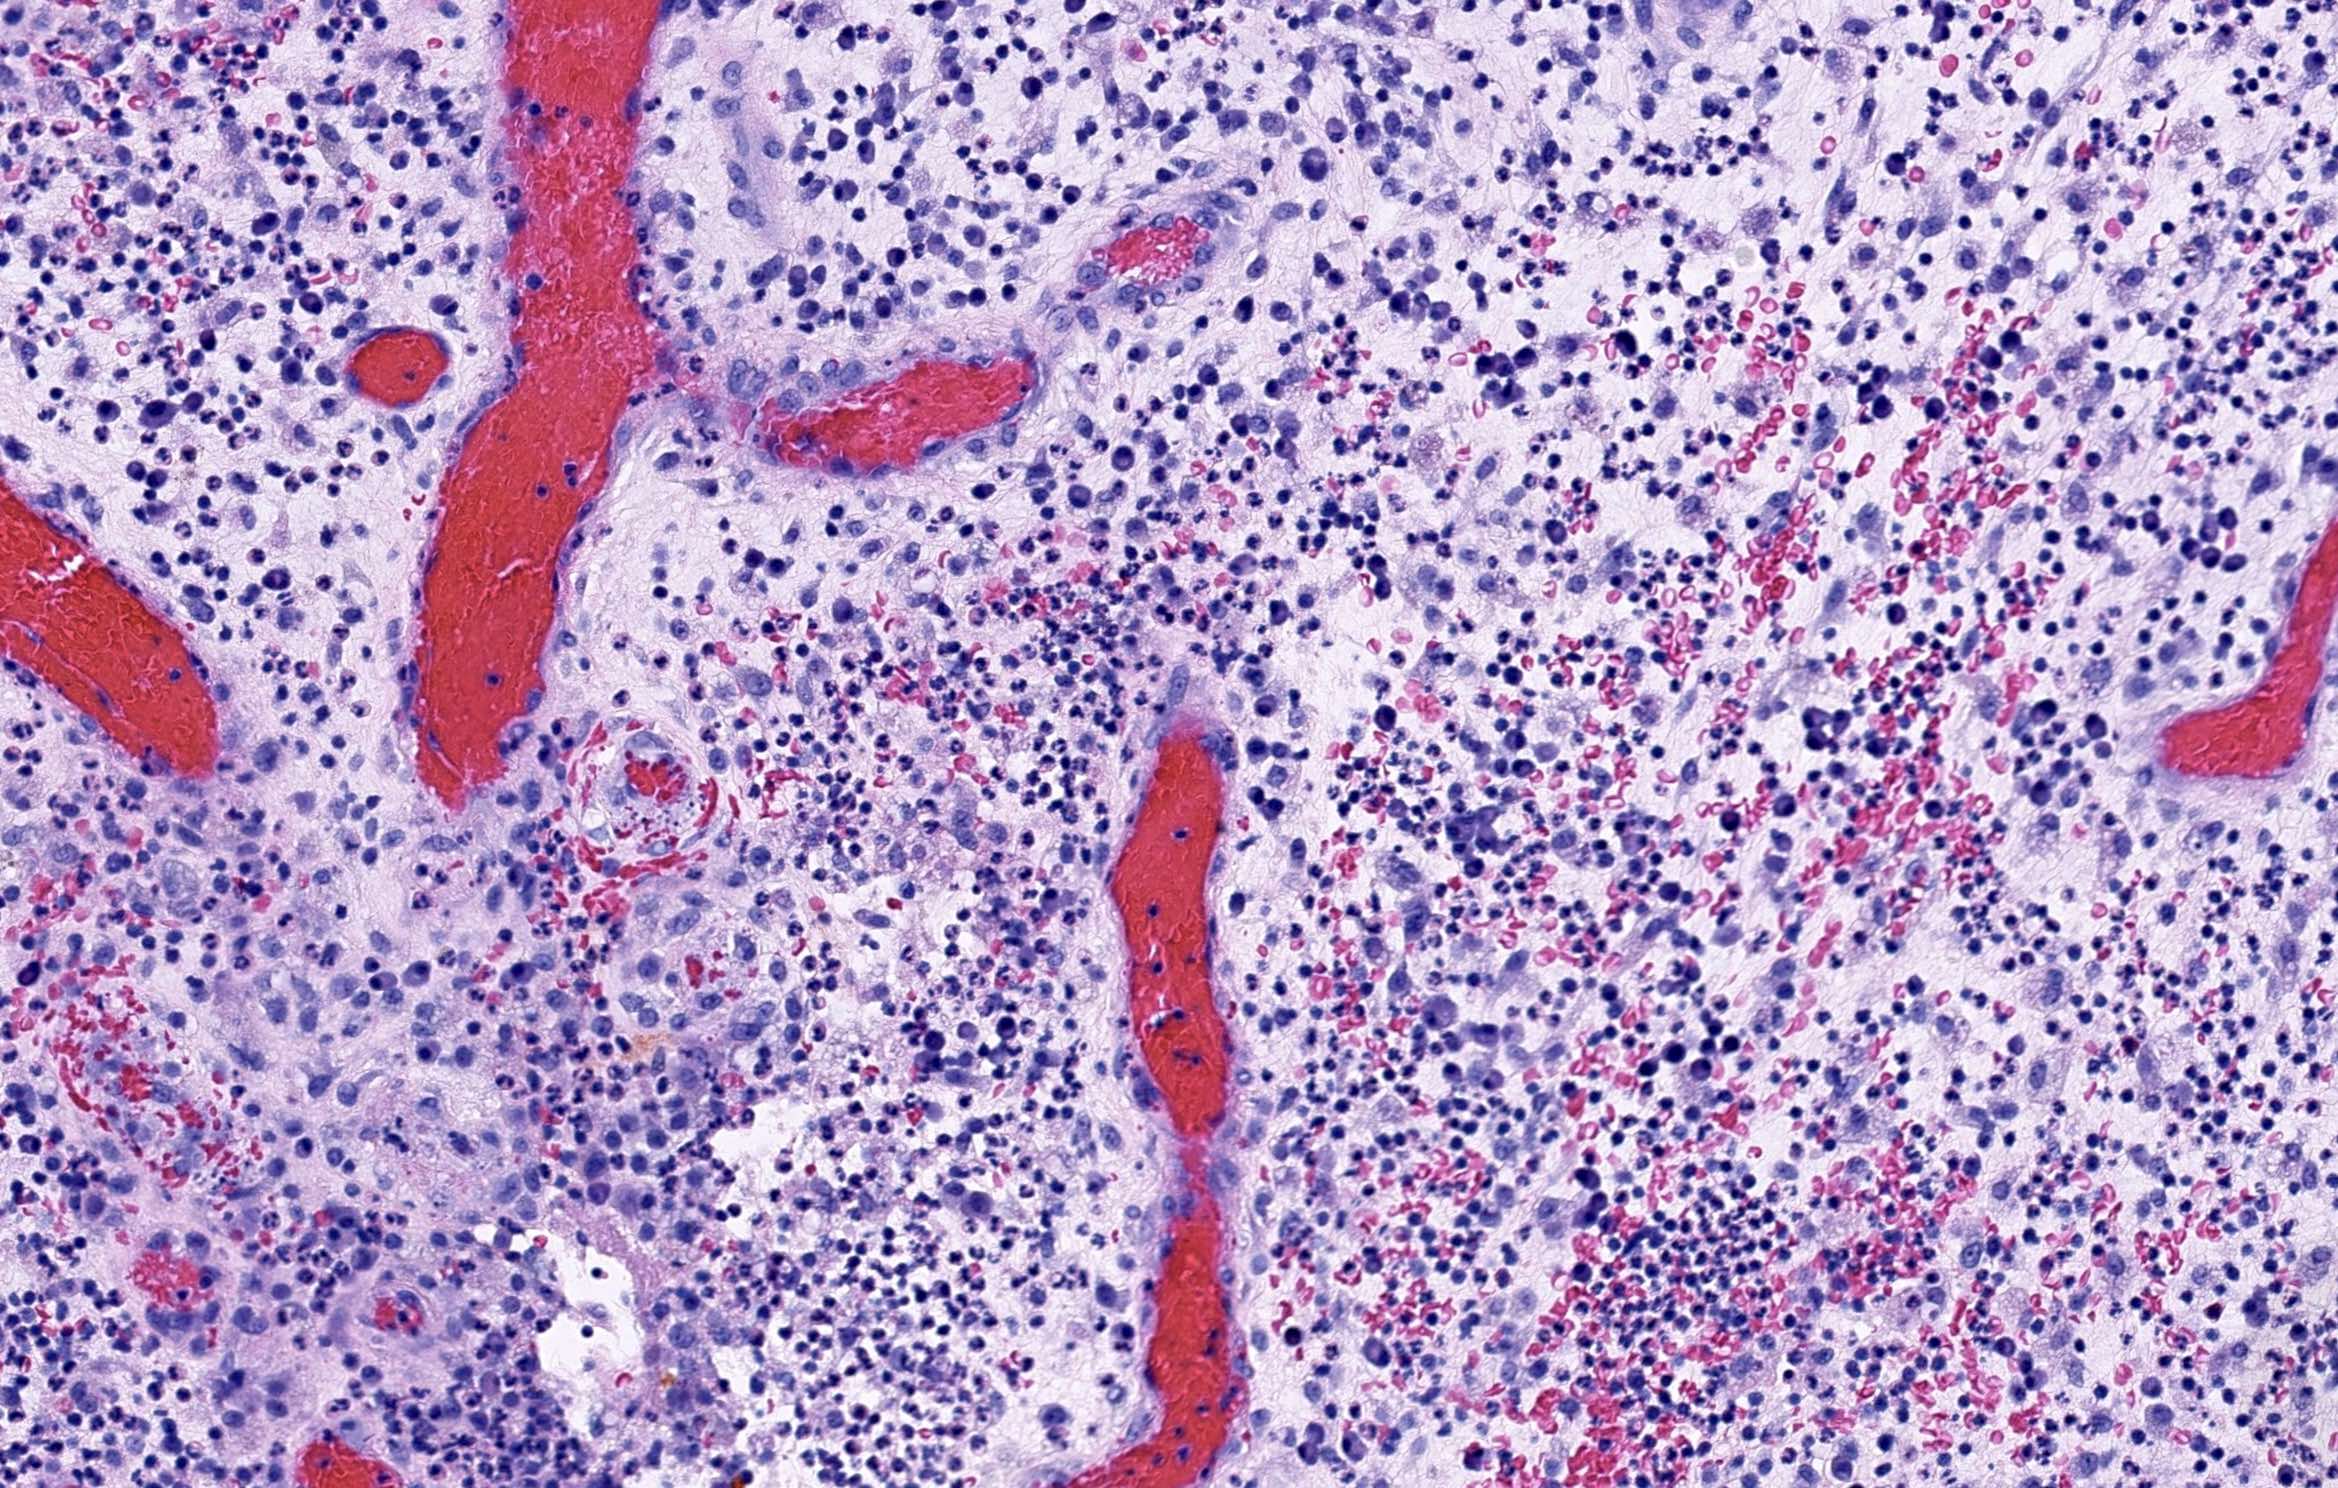

Microscopic (histologic) description

- In early lesions: follicular hyperkeratosis, hyperplasia of follicular epithelium and perifolliculitis (Br J Dermatol 2011;164:367)

- Dermal mixed inflammatory cell infiltrate, sometimes extending into the subcutis (Br J Dermatol 1990;122:763)

- Neutrophilic abscesses, which may connect with squamous epithelium lined cysts and sinus tracts that extend to the skin surface (Br J Dermatol 1990;122:763)

- Cysts and sinus tracts contain laminated keratin and occasional hair follicles (Br J Dermatol 1990;122:763)

- Granulation tissue with occasional foreign body giant cells present in ~25% of cases (Histopathology 1993;23:111)

- Inflammation involves apocrine glands in a minority of cases (J Am Acad Dermatol 1996;34:994)

- Dense fibrosis surrounding areas of follicular rupture

Microscopic (histologic) images